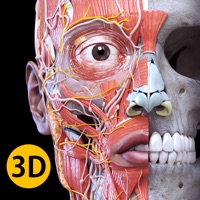

1. "Anatomy - 3D Atlas" es una aplicación dirigida a estudiantes de medicina, médicos, fisioterapeutas, personal sanitario, enfermeros, entrenadores de atletismo y, en general, a cualquier persona interesada en ampliar sus conocimientos sobre anatomía humana.

5. "Anatomy 3D Atlas" te permite estudiar la anatomía humana de una manera fácil e interactiva.

6. A través de una interfaz simple e intuitiva podrás observar cada una de las estructuras anatómicas desde cualquier ángulo.

7. y el estudio de partes individuales o de grupos de aparatos, así como de las relaciones entre los diferentes órganos.

8. Los modelos anatómicos en 3D resultan especialmente minuciosos y ofrecen texturas de hasta 4k de resolución.